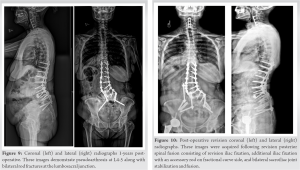

Pre-operative extension radiographs of the lumbar spine (Fig. 1) and computed tomography (CT) imaging (Fig. 2) demonstrated thoracolumbar curve measuring approximately 50° from T11-L5, a right hemivertebrae at L5, a 9 mm of lateral listhesis at L3-4, 15° of lumbar lordosis, and asymmetric disc height loss from L1-S1.

The objectives of this study were to (1) illustrate an example of successful surgical treatment of a patient with hemivertebrae using custom patient-specific implants at multiple spinal levels and (2) compare this case a to a similar case that utilized standard implants. The patient in Case 1 suffered from chronic low back pain due to CS and a right wedge vertebra. Following lumbar decompression and fusion using customized 3D-printed implants, the patient reported significant improvement in her pain and posture (Fig. 6). Given the anatomic complexity of these patients, the development and utilization of customized implants allowed for an excellent endplate apposition without the need for extensive bony resection, which would not be possible with standard interbodies. To our knowledge, this is the first reported case demonstrating the treatment of CS using 3D-printed personalized spinal implants for multiple spinal levels. Studies evaluating the efficacy of personalized spinal implants are largely limited to case studies. Two of these studies reported the use of these implants in the treatment of congenital spinal disorders. Mobbs et al. [14] presented a 52-year-old woman with an 18-month history of back pain. Similar to our patient, their patient was found to have a congenital hemivertebra at L5 (Fig. 1 and 2) with degenerative changes that was treated with lumbar decompression and fusion with a personalized spinal implant. However, while only the L4/L5 segment was fused in Mobbs et al. case, the patient in our case underwent L3-S1 ALIF and posterior instrumentation T10-Pelvis (Fig. 4 and 5), demonstrating increased severity and unique complexity in our case. In another study [15], a 34-year-old man presented with a 3-year history of bilateral L5 radiculopathy caused by bilateral L5 pars defect, L5/S1 degenerative disc disease, and severe foraminal stenosis. Anterior lumbar interbody fusion surgery was performed with custom 3D interbodies. Again, our case differed from this case in complexity of procedure and medical history as we performed a multilevel deformity surgery using multilevel customized implants. To address our second objective, we compared Case 1 to Case 2, where the patient underwent an index lumbar decompression and fusion for CS (Fig. 7 and 8) using standard titanium implants. At 2-year post-operative, the patient in Case 2 presented with worsening sacroiliac pain with the evidence of rod fracture and pseudoarthrosis at L4-L5 (Fig. 9). Revision surgery resulted in improved pain and mobility (Fig. 10). Development of pseudoarthrosis and the need for revision surgery in Case 2 may be explained by the decreased surface area available for fusion, decreased contact of the implant with the bone, thus decreased on-growth and through-growth resulting in decreased osteointegration, and stability as compared to Case 1, which utilized custom implants. While larger, randomized, controlled studies are still needed to gain knowledge pertaining to long-term outcomes in comparison to traditional, non-customized implants, existing biomechanical and animal investigations of customized implants suggest they will provide improved outcomes and increased surgical safety and efficiency. In a study evaluating the biomechanical properties of titanium cages in cervical spine surgery, Fengbin et al. found that implants with increased end plate contact surface area resulted in decreased loss of height of fused segments, lower rate of subsidence, and lower scores of neck pain [16]. During an en bloc resection of L5 vertebral body with single lesion, Mobbs et al. compared reconstruction using a 3D patient-specific implant and an off-the-shelf implant at the same spinal level intraoperatively. The 3D patient-specific implant resulted in decreased time to implant, reduced radiographs required to determine the position of implant, improved end plate fit, and more uniform loading compared to the off-the-shelf implant [5]. From a safety perspective, 3D-implants seem to provide benefit over off-the-shelf implants as they avoid osteotomies required with off-the-shelf implants, thus decreasing operative time and blood loss, as well as allow for pre-planned screw trajectories which decrease the chance of damage to blood vessels, nerves, and the spinal cord [17]. The utility of 3D customized implants in allowing surgeons to operate on native anatomy will be safer, quicker, and result in increased osteointegration and bone/implant interface.